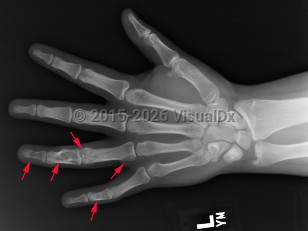

Enchondroma in Child

Causes / typical injury mechanism: Enchondroma is a benign, hyaline-cartilage producing tumor located in the medullary canal of the diaphysis or metaphysis of long bones.

Ollier disease and Maffucci syndrome are nonhereditary conditions that present as multiple enchondromas. Ollier disease involves multiple asymmetric enchondromas of the digits. It is most commonly seen in childhood. These slow-growing tumors usually stop growing after puberty, but masses can create deformity and limb asymmetry. Pathologic fractures may be seen. Ollier disease has a 15%-20% risk for secondary chondrosarcoma.

Classic history and presentation: The proximal phalanx is the typical location. These tumors are also common incidental findings in the distal femur, proximal humerus, and tibia. Mean length is usually less than 5 cm.

Prevalence: Enchondroma is a latent lesion that comprises 15%-25% of cartilage tumors. It is the most common hand tumor, accounting for 90% of cases. Enchondroma usually presents in the third and fourth decades of life and occurs equally between both sexes.

Pathophysiology: Enchondroma pathophysiology is believed to involve incomplete endochondral ossification in which physeal remnants become entrapped in the medullary cavity of the metaphysis and proliferate. In the hand, enchondromas are typically diagnosed after a pathologic fracture. Elsewhere, they are typically an asymptomatic incidental finding on x-ray or advanced imaging performed for other reasons. Pain is usually due to a nearby abnormality rather than the tumor itself.